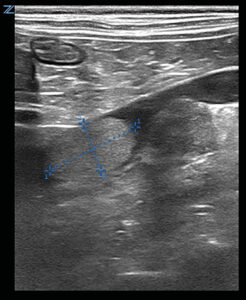

En el abdomen la glándula adrenal derecha presenta pérdida de estructura y una anchura de 17 mm; comprime la vena cava caudal, que presenta un trombo (imágenes 4 y 5). Estos hallazgos sugieren cardiomiopatía hipertrófica secundaria a hipertensión arterial sistémica y neoplasia adrenal derecha con trombosis venosa.

Imágenes ecográficas de la glándula adrenal derecha aumentada de tamaño, con pérdida de forma normal y estructura intravascular hiperecogénica adherida a vena cava caudal, compatibles con neoplasia adrenal y trombo en dicha vena.